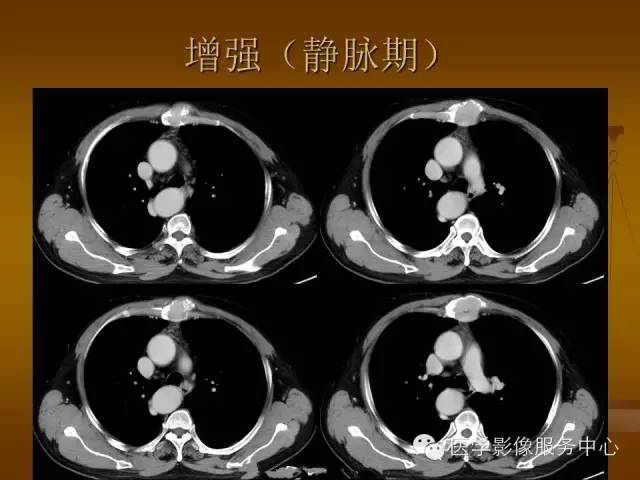

增强扫描可见病灶轻中度强化,一般于静脉期达峰值。